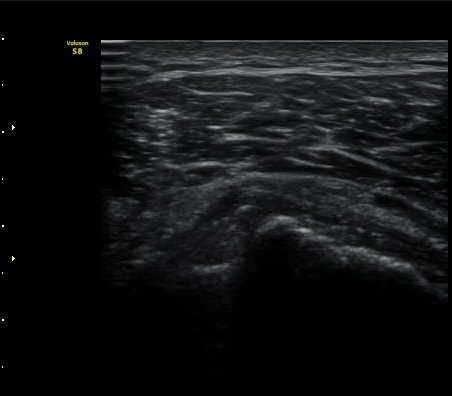

±Ø»ó°Ç Á¾´Ü¸é°Ë»ç½Ã ±Ø»ó°Ç ºÎÂøºÎ¿¡ Àú¿¡ÄÚ ºÎÁ¾°ú ¹Ì¼¼ÇÑ °Ç ¿¬°á¼º ¼Ò½ÇÀÌ

°üÂûµÊ (±×¸² 1, 2, 3 )